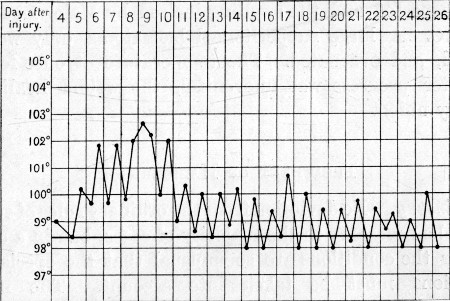

1. Case of Axillary Hæmatoma, Blood Temperature 119

2. Case of Hæmothorax with Recurrent Hæmorrhages 395

3. Primary and Secondary Rises of Temperature in Hæmothorax, Recovering Spontaneously 402

4. Secondary Rise of Temperature in Hæmothorax 403

5. Falls of Temperature in Hæmothorax following Paracentesis 404

6. Secondary Hæmothorax, Spontaneous Fall of Temperature 405